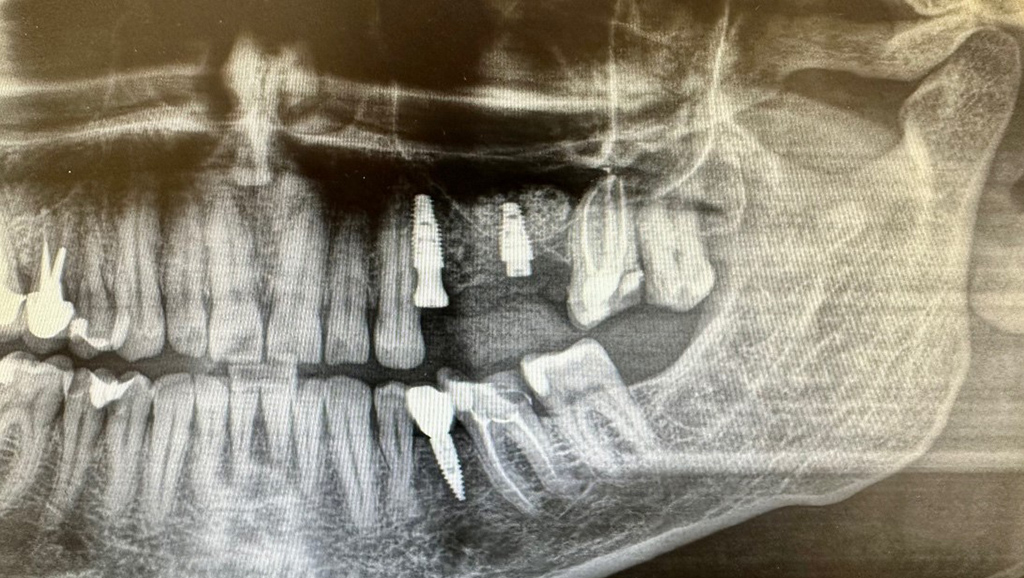

Zdjęcie rtg po zabiegu implantacji z zabiegiem „sinus lift” lewej zatoki szczękowej

zdjecie rtg po zabiegu implantacji